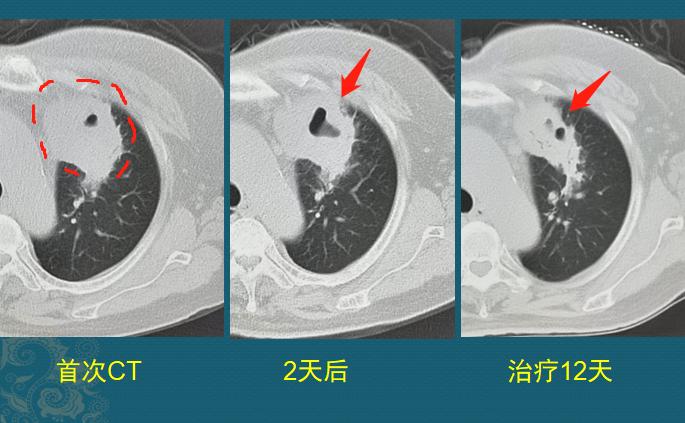

3.吸入性金葡菌肺炎,常可见实变区内形成脓肿,以下肺叶多见,空洞在实变区中央,内壁光滑,外壁因为周围炎症而常常模糊,有时候空洞内脓液没有完全排空,可以气液平面。如下图,70岁女性,吸入性金葡菌感染:

咳嗽、发高烧住院,左上肺脓肿,2天后咳出大量脓稠痰液,复查CT出现空洞(病情变化快),对抗生素敏感,治疗12天后明显吸收好转。这种化脓性感染,只靠身体的自愈力是远远不够的。